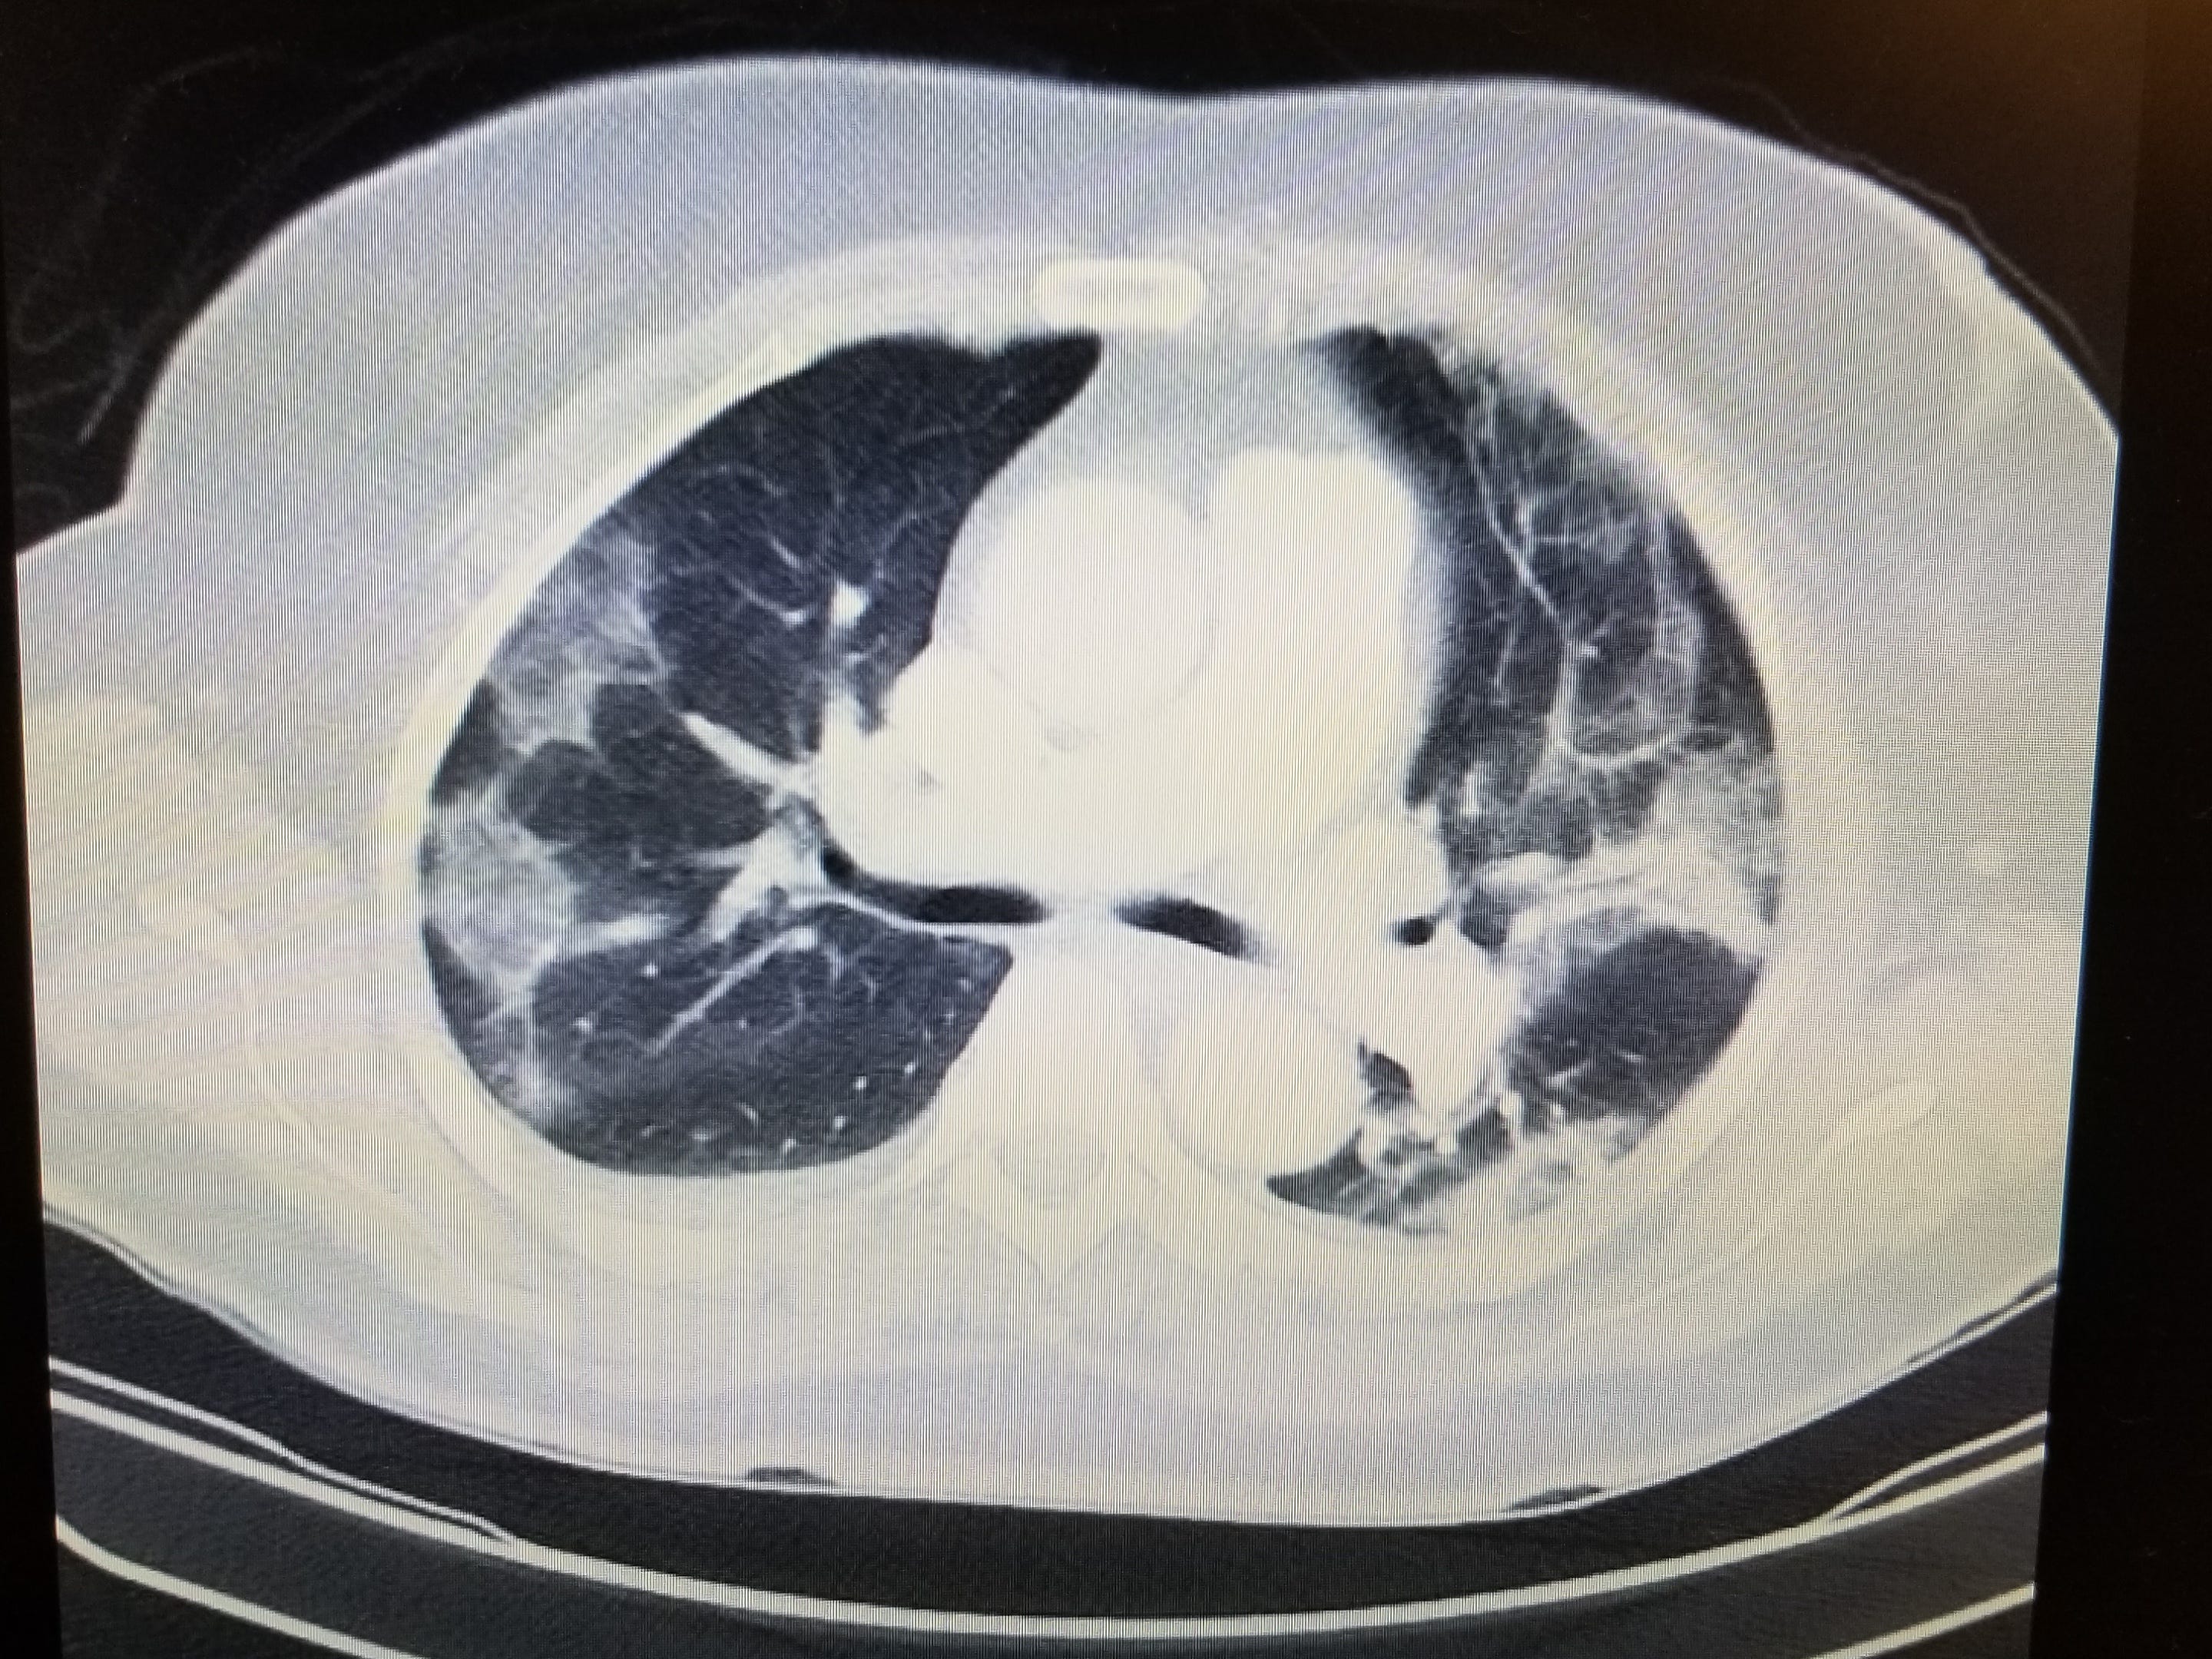

Steroids for severe pulmonary infections: Review

JAMA review supports the new paradigm of steroids-for-most in the ICU